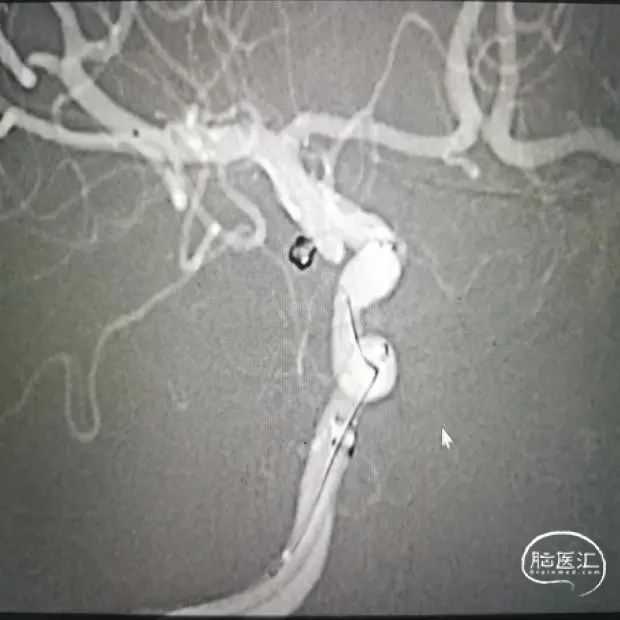

栓塞第一枚弹簧圈

栓塞第二枚弹簧圈

穿刺右股动脉,造影证实右侧后交通动脉瘤,微小宽颈动脉瘤,5F多功能造影管带通桥银蛇6F-115直奔主题,进入右侧颈内动脉,路径图指引下微导管引导支架微导管到达预定位置,然后通过微导丝引导栓塞导管进入瘤腔,分别依次填入3D2*4cm、1.5*2cm、1*1cm三枚弹簧圈,栓塞结束后造影显示动脉瘤致密栓塞,依次撤出器械,结束手术。